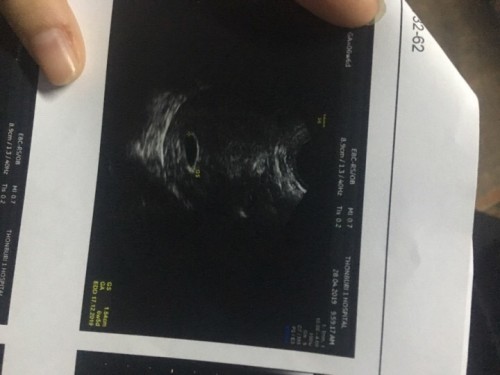

วันนี้ไปซาวมาค่ะ คุณหมอบอกว่าอายุครรภ์ 6week5day ตัวอ่อน0.24cm ถือว่าเล็กไปไหมคะ เพราะไปอ่านในเน็ตมาเค้าก็ประมาณ0.58ค่ะ เราเลยกังวลมาก ขนาดถุงตั้งครรภ์ 1.54ค่ะ เครียดมากค่ะ???